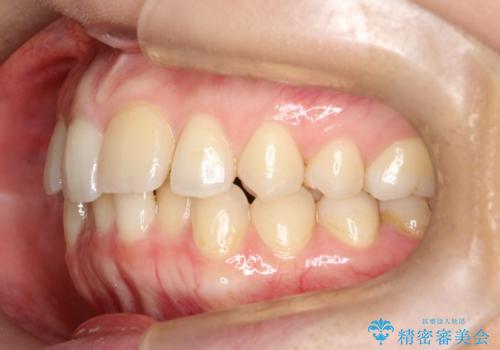

矯正後の後戻り インビザラインで改善

- 前歯のガタツキが気になると来院されました。

マウスピース矯正治療を選択しました。

前歯のガタツキを改善する治療法として、マウスピース矯正が適していることが多いです。

マウスピース矯正は、金属製のブラケットやワイヤーを使用せずに、透明なマウスピースを装着して歯を移動させる方法です。そのため、目立たず、痛みも少ないです。